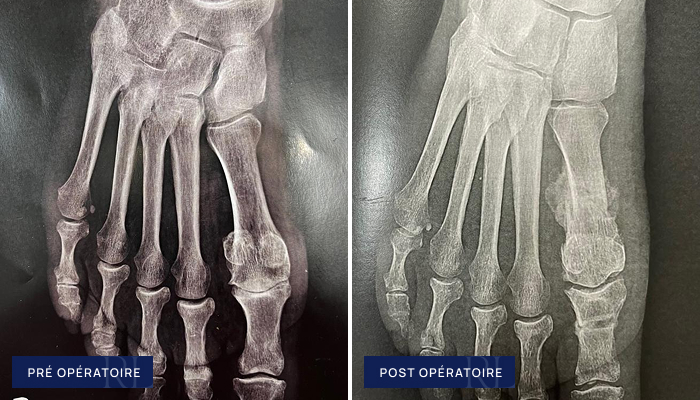

Hallux Rigidus (Arthrodèse)

À gauche : Usure globale sévère de l’articulation du gros orteil (arthrose stade IV de l’articulation métatarso phalangienne de l’hallux )

À droite : Arthrodèse du gros orteil (double vissage percutané)